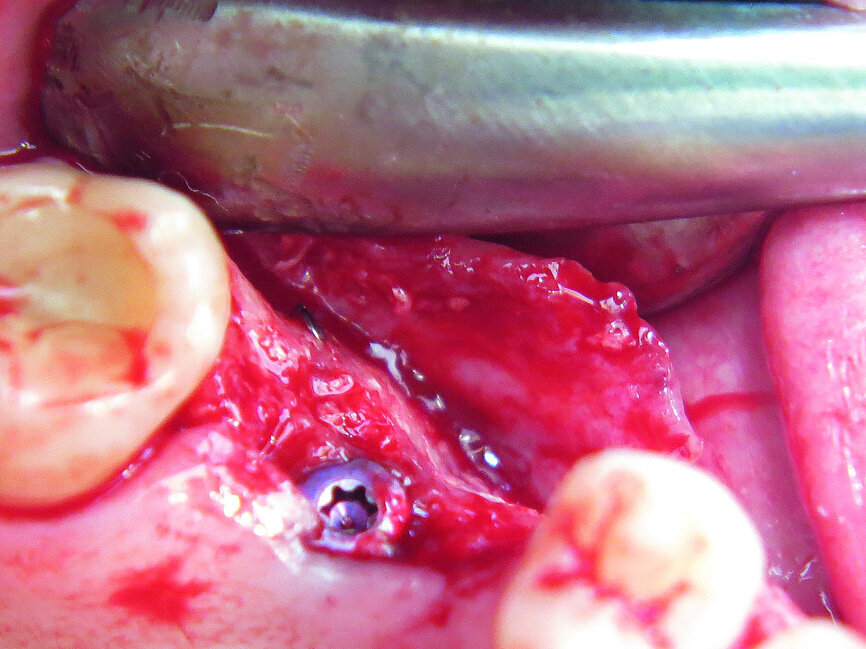

Fig. 15: Implant fixed with pins.

The first was a 51-year-old patient who smoked 30 cigarettes per day and suffered from diabetes and stress (Figs. 1–8). The second was a 76-year-old male patient in good physical condition who smoked 40 cigarettes per day. He underwent reconstruction of the premaxilla (Figs. 9–13). The third was a healthy female patient of 24 years of age who smoked 20 cigarettes per day. She required a sinus lift in region #25 (Figs. 14–21). The patients were informed of the intended process in detail and signed the surgical protocol containing information concerning possible risks of failure and complications, as well as information on the alloplastic and synthetic materials to be used.

After four weeks, a site-specific full-thickness flap was raised buccally in Case 3 by vertical releasing incisions without including the papillae of the adjacent teeth (Figs. 16–19). In the aesthetic zones, no vertical incisions were made. In order to optimise the situation of the soft tissue, we placed a pedicle flap (connective tissue graft from the palate). After atraumatic flap elevation, the granulation tissue was removed.